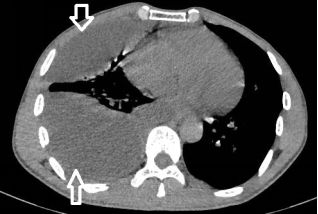

蜘蛛网胸水(包裹性胸腔积液),在胸腔镜下是什么鬼样子的呢?

一大包胸水,看着是不是很好抽?Ease,轻松搞定!

为什么会酱紫?明明有胸水啊!明明确实有胸水,只不过......

且看胸腔镜:

胸腔里面这么多分隔,你能保证你的针在哪个小分隔里面?除非你有孙悟空的火眼金睛!

下面这种胸水,看着也挺多,但是,也是反重力的存在:貌似水往低处流!

在胸腔镜下,是“蜘蛛网+蜂窝状”般的变态存在。